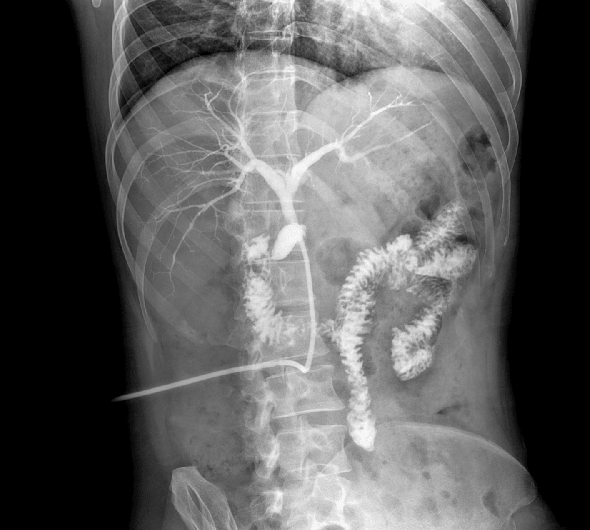

原厂优质影像链,搭载直接生长式碘化铯非晶硅平板,带来更加清晰锐利的图像效果。